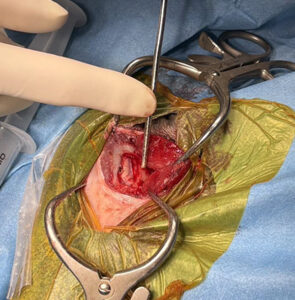

ご家族と相談の結果、できる治療をしてあげたいとのことで、開頭による腫瘍摘出術を実施しました 。病理診断は当初の予測通り、猫の脳腫瘍で最多の髄膜腫でした 。

術後、脳への圧迫が取れたことで経過は極めて良好であり、発作は出なくなりました。現在は完全休薬に至っており、発作のない穏やかな生活を取り戻してくれています。